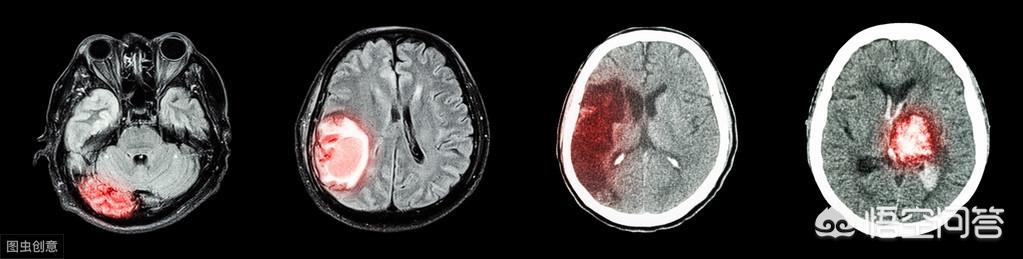

脳出血脳出血とも呼ばれ、脳実質内の血管が非外傷性で破裂し、出血を起こすものである。

脳出血は医学用語で脳梗塞とともに脳卒中と呼ばれる脳出血のことで、比較的重い病気です。皆さんの中にも脳出血にかかったことのある人は多いでしょうし、皆さんの村にも、病気で歩いたり話したりできない人の中には、脳出血にかかったことのある人がいるかもしれません。

脳出血は通常、脳実質の自然出血であり、外傷が原因ではない。

脳出血は、実際には脳内出血であり、血管の硬化や閉塞により脳内の血管が破裂して起こる病気で、その死亡率は極めて高い。ひとたび脳出血を起こすと、半身不随など身体に大きなダメージを与え、昏睡状態に陥り死に至ることもある。